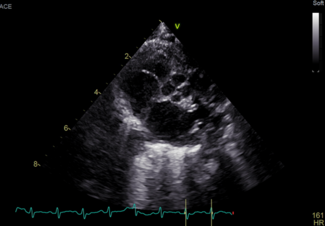

A 3-day-old male neonate was referred to our hospital for a cardiac echocardiogram.